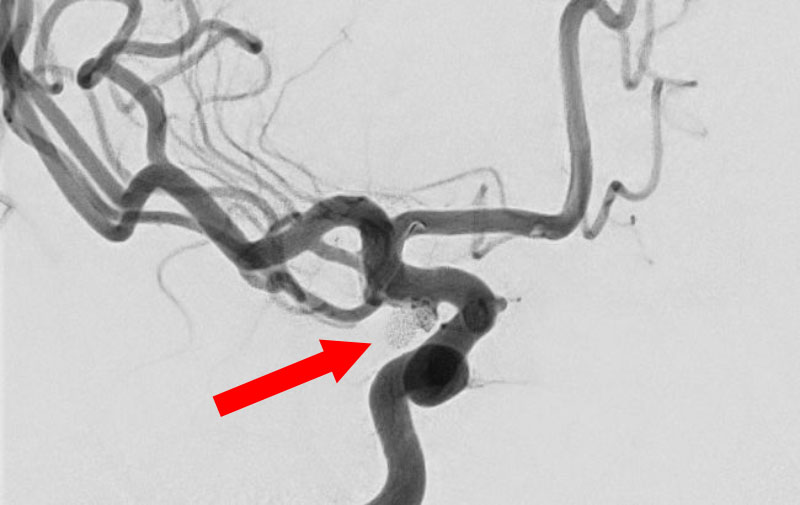

No.1596 手術前